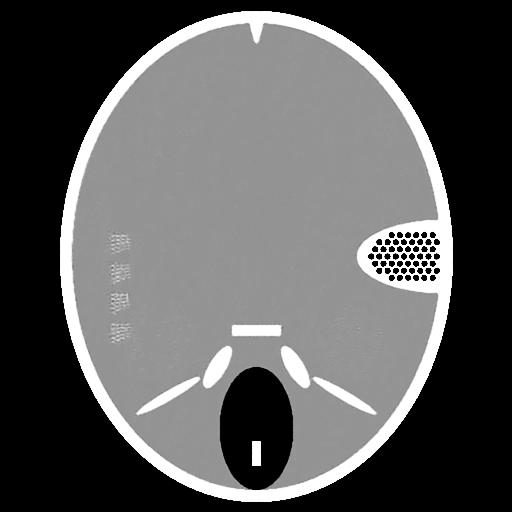

Fig.4 shows the limited-angle CT reconstruction results of the Forbild phantom using different methods, where the projection angle goes from to with increments. Fig.4a presents the reconstruction result of the steepest descent algorithm. Due to the missing projections, the reconstruction result suffers from severe artifacts. Fig.4b shows the result of the CDIP algorithm using Fig.4a as input. It is evident that CDIP cannot remove the existing artifacts in Fig.4a and, in fact, further degrades the reconstruction accuracy. On the contrary, the output of the original DIP method (Fig.4c) significantly suppresses the artifacts and achieves a much better result. Finally, Fig.4d shows the reconstruction result of our proposed method (SDIP), which is very close to the ground truth. Its details will be introduced in Section III-C.

(a) Steepest Descent (23.29dB)

(b) CDIP (19.82dB)

(c) DIP (29.88dB)

(d) SDIP (38.61dB)